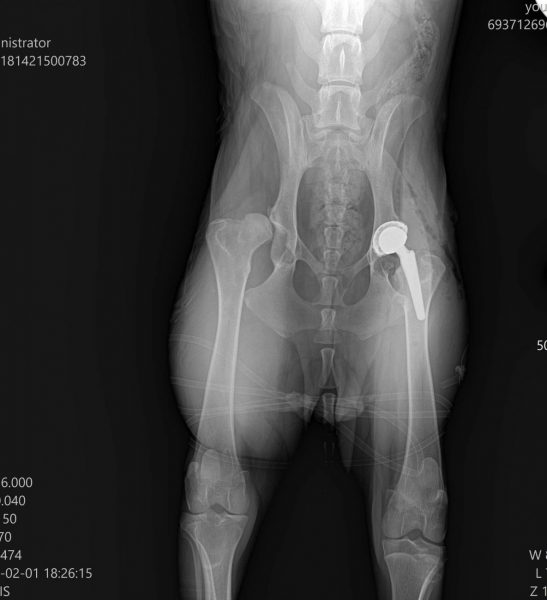

Η ακτινογραφία του μετά το χειρουργείο. Δεξιά φαίνεται η τεχνητή ενδοπρόθεση.

Η ολική αρθροπλαστική ισχίου (THR) θεωρείται ως η πλέον προηγμένη και αποτελεσματική χειρουργική λύση για την αποκατάσταση της κινητικότητας των σκύλων με σοβαρή δυσπλασία ή εκφυλιστική αρθροπάθεια.

Κατά την επέμβαση αφαιρείται η πάσχουσα άρθρωση και αντικαθίσταται με τεχνητή ενδοπρόθεση, συνήθως από τιτάνιο.